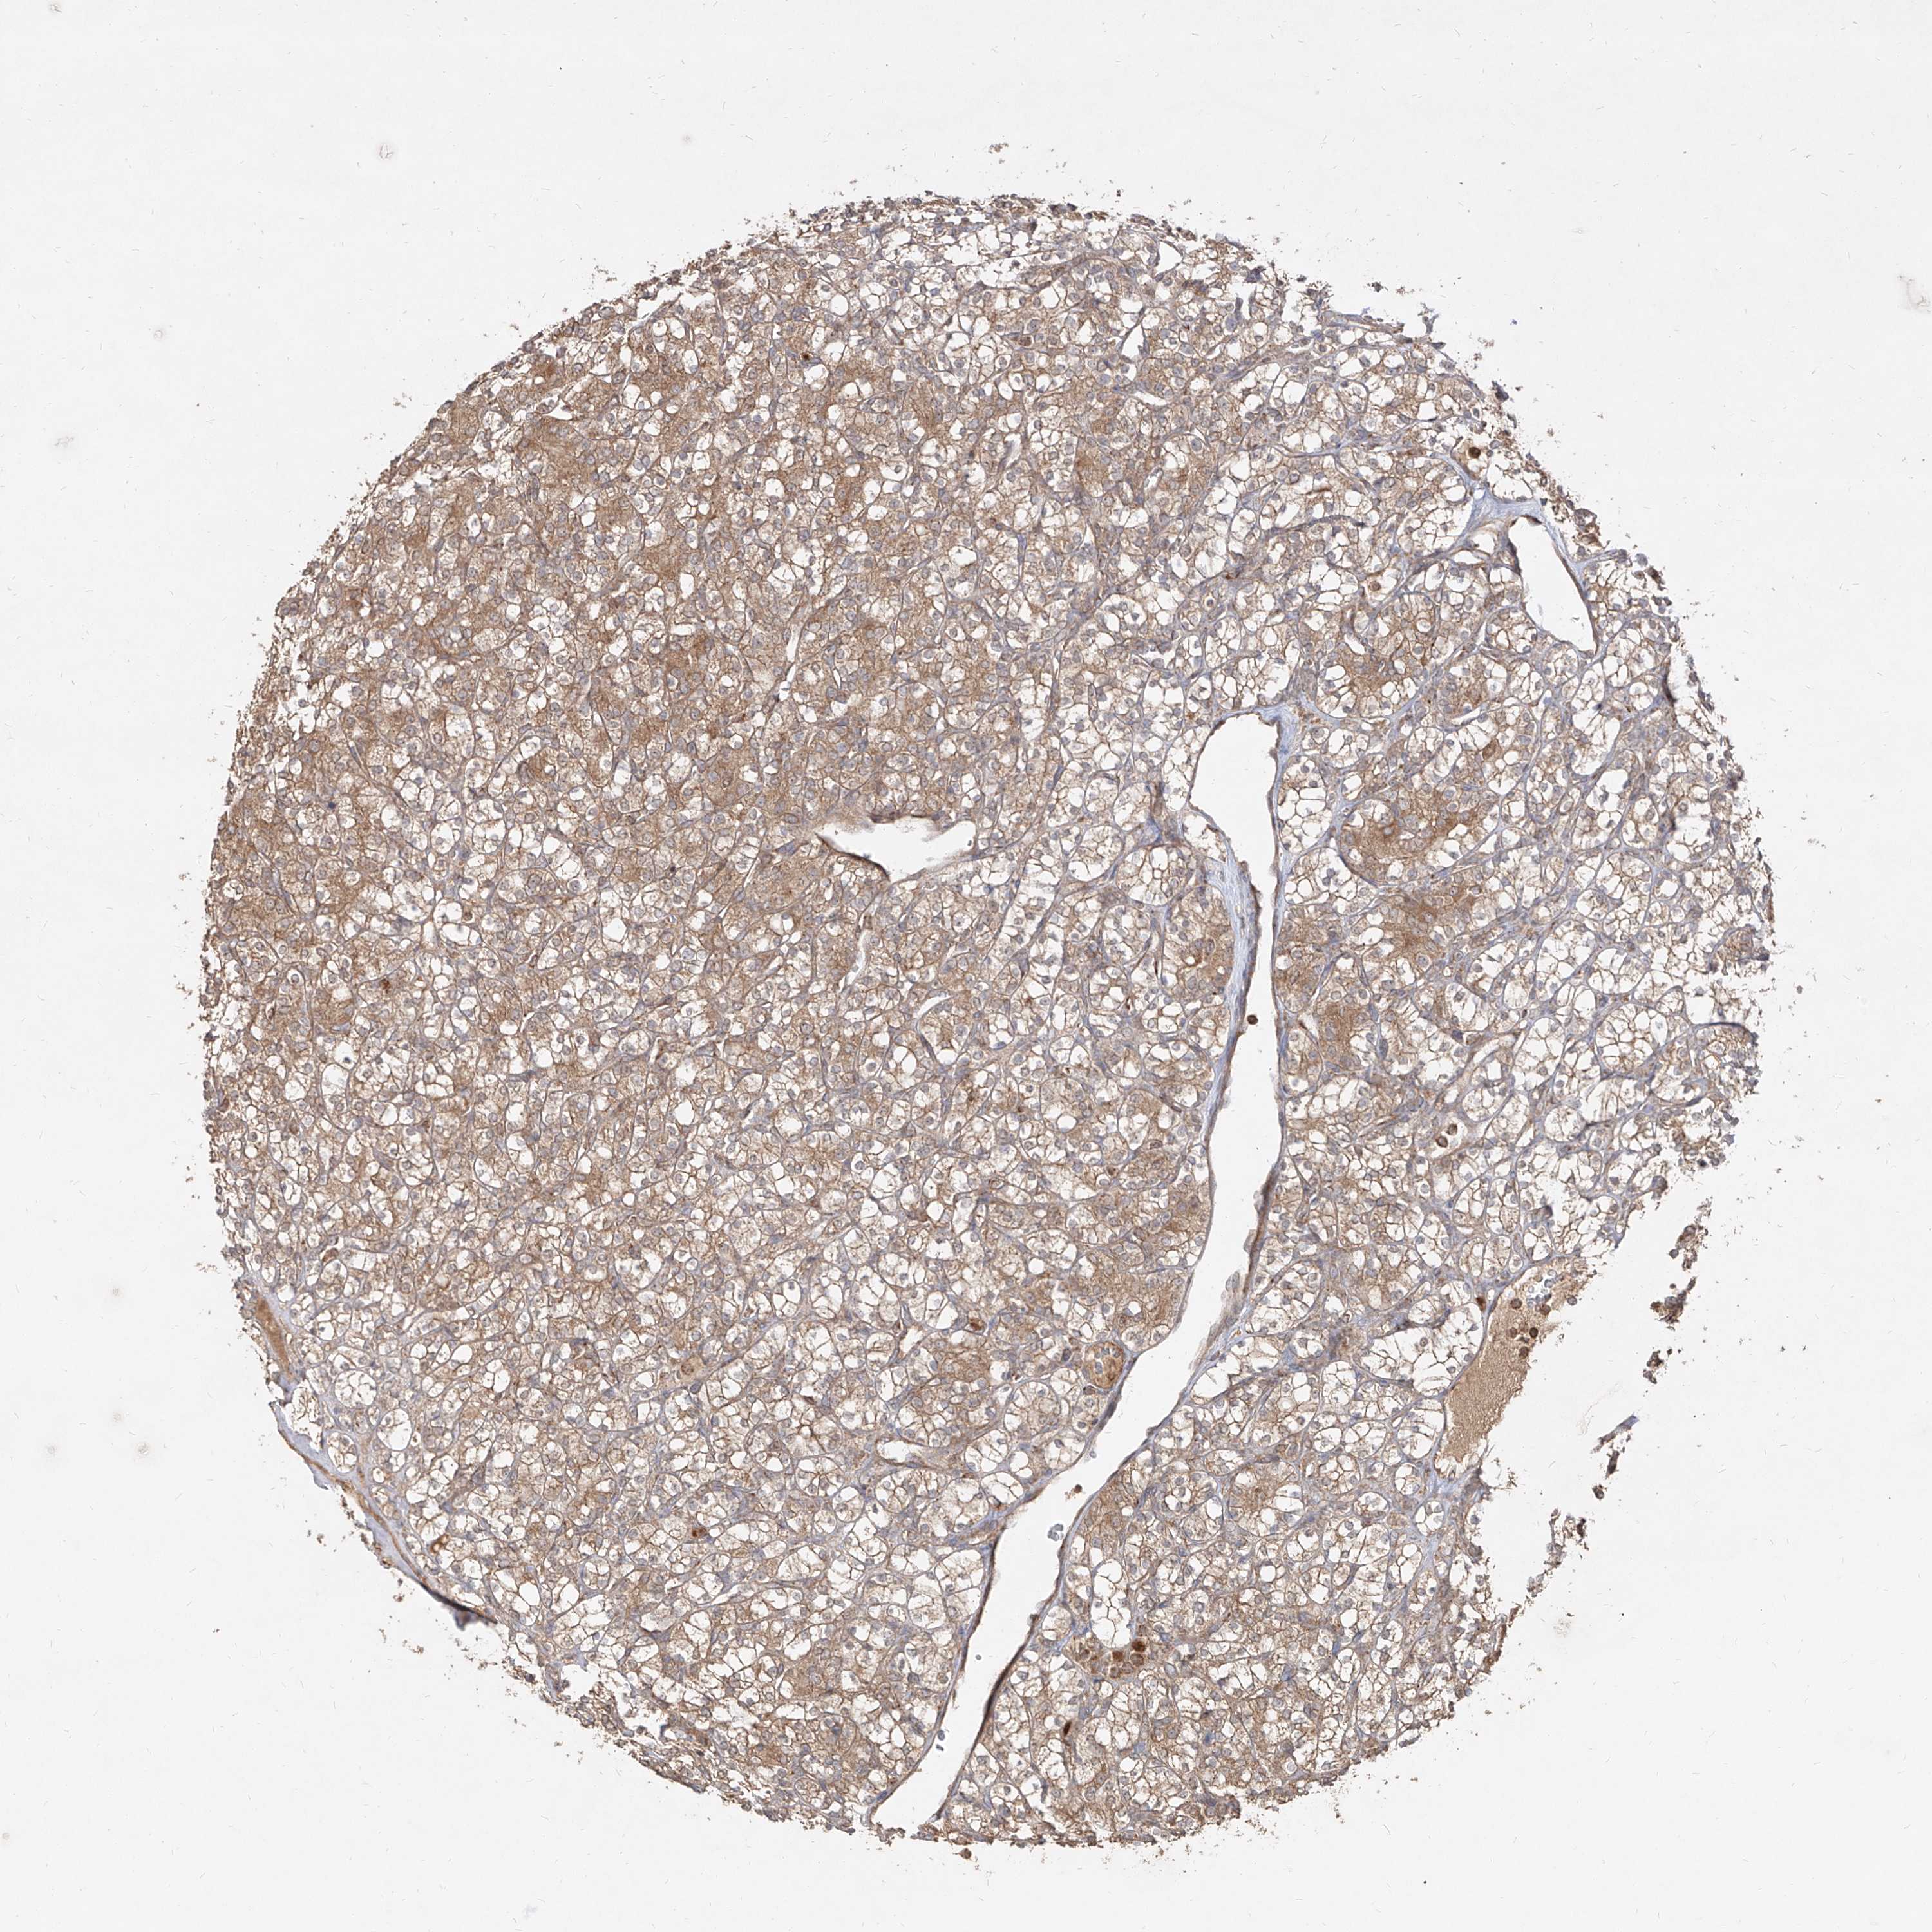

CANCER RENAL CANCER Show tissue menu

KICH TCGA KIRC TCGA KIRC VALIDATION KIRP TCGA PROTEIN RCC CPTAC PROTEIN EXPRESSION

AIM2 is potential prognostic, high expression is unfavorable in Kidney Renal Clear Cell Carcinoma (TCGA)

: 3.74

Average pTPM 2.7

Number of samples 521